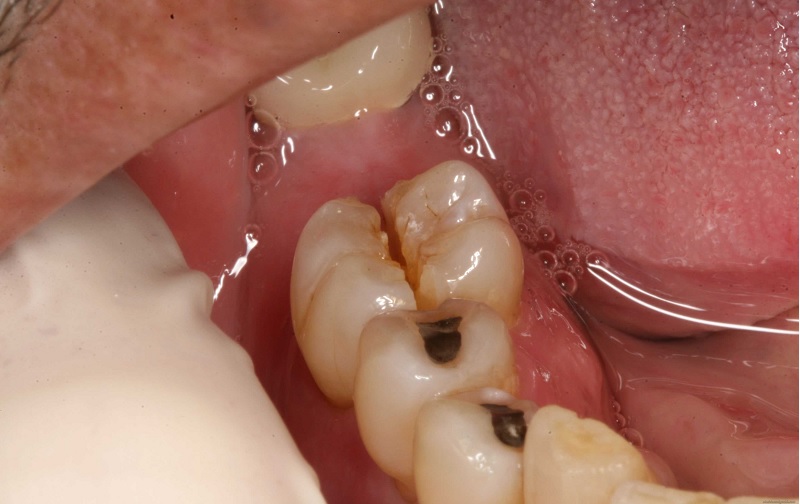

những chiếc răng trông giống như gốc cây màu nâu đen – điều này cho thấy trẻ đã bị sâu răng.

Sâu răng có thể biểu hiện như:

một dải màu trắng xỉn màu hình thành trên bề mặt răng gần với đường viền nướu – đây là dấu hiệu đầu tiên và thường khó phát hiện

một dải màu vàng, nâu hoặc đen trên bề mặt răng gần với đường viền nướu nhất – điều này cho thấy sâu răng đang nặng hơn